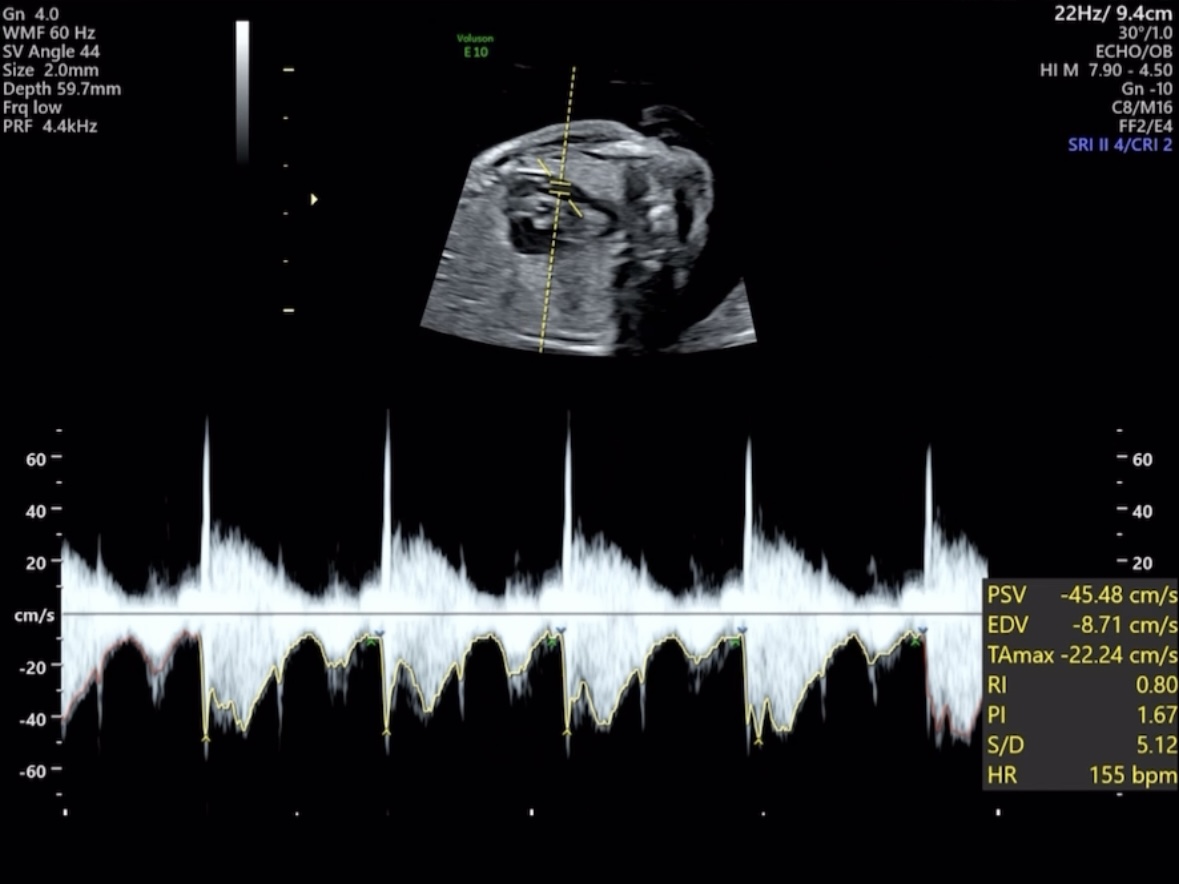

심장

심장은 이해하기 어려웠다. 2심방 2심실의 판막이 제대로 닫혔는지, 혈류가 각각에 잘 흐르는지 위치별 초음파를 봤다.

정상적으로 판막이 잘 닫혔고 정맥/동맥이 잘 흐르는걸 확인했다.